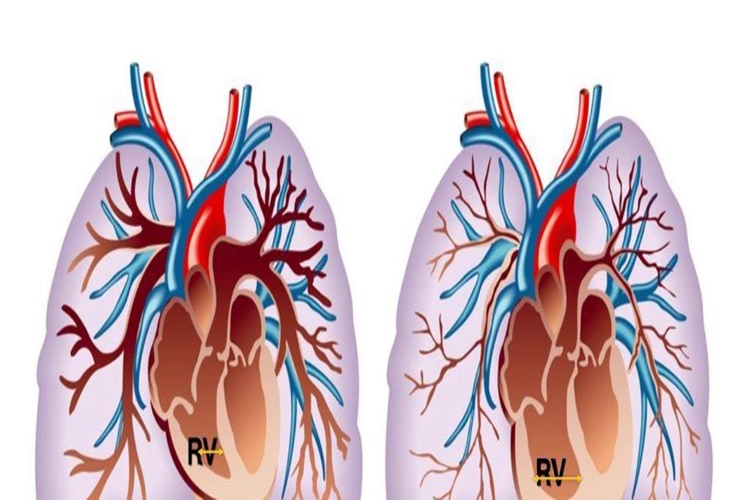

Burun polipleri tedavi edilebilir bir rahatsızlıktır ve başlarda tehlikeli olarak belirtilmez. Ancak tedavi edilmeyen burun polipleri zaman içinde tehlike arz eder. Burun polipleri burunda kanser oluşumuna neden olabilir. Burunda oluşan tümörler kontrol alınmadığında ise tümör diğer dokulara yayılır ve lenf ya da kan dolaşımı üzerinde tehlike oluşturmaya başlar.